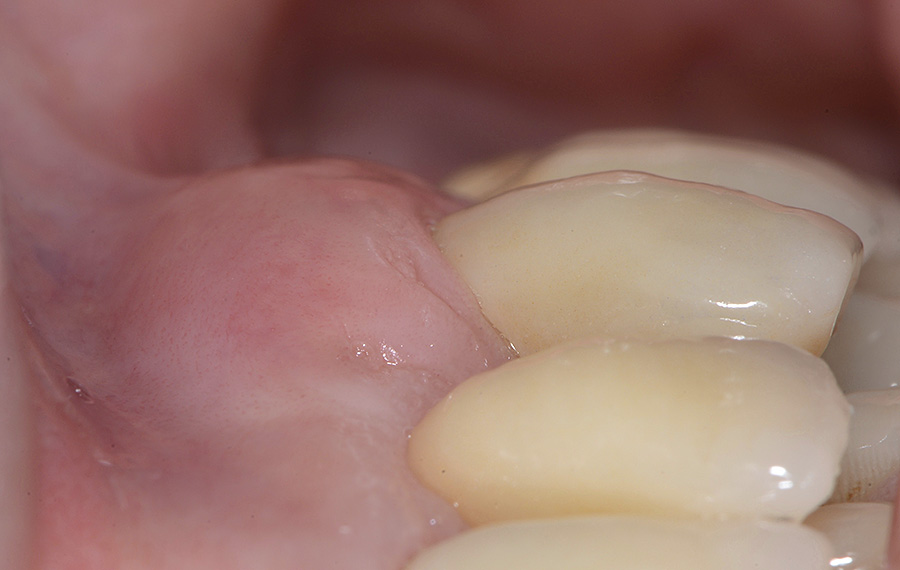

PREMESSA: in seguito all’estrazione dell’incisivo laterale superiore di destra, resasi necessaria per cause batteriche, si decide di affrontare il caso con il posizionamento di un impianto in sostituzione dell’elemento mancante dopo guarigione del sito infetto. Con tecniche rigenerative sia dei tessuti ossei mancanti a causa dell’infezione pregressa, sia dei tessuti gengivali che appaiono inizialmente troppo spostati in alto, si ripristina una corretta morfologia delle parabole (contorni) gengivali e delle papille interdentali (triangoli di gengiva tra due denti vicini).

Vengono utilizzati 2 tipi di provvisori: il primo, cementato ai denti vicini, viene utilizzato dal momento dell’estrazione del dente fino ad impianto osteointegrato (circa 6 mesi); il secondo, avvitato direttamente all’impianto, ha una funzione di prova estetica ma soprattutto di guida per la maturazione dei tessuti gengivali peri-implantari portandoli verso la maturazione completa prima di posizionare la corona finale in disilicato di litio.